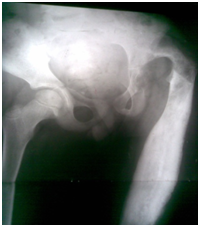

Figure 6 After removal of ex fix and application of Hip Spica cast.

Figure 7 After completion of treatment and removal of hip Spica cast.

Figure 8&9 Compare initial Radiograph and after completion of treatment.